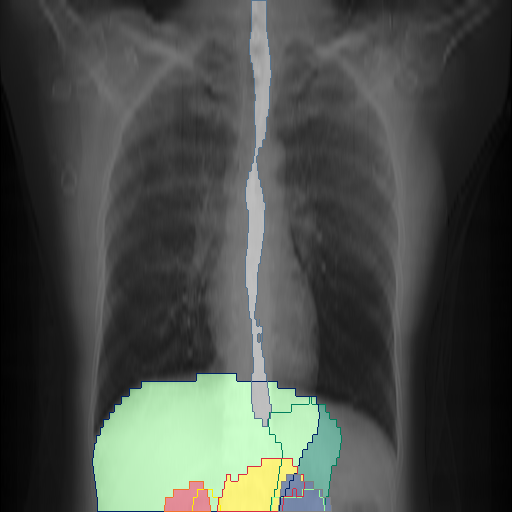

We show qualitative results for frontal projections in Fig. 2. We show a subset of classes belonging to the supercategories lungs, vascular systems, bones, and abdomen/digestive system. The predictions show minor deviations at the boundaries of the individual classes of the respiratory and vasculature system, while some inaccuracies become visible in the abdominal area. The qualitative results for the lateral projections are displayed in Fig. 2. Akin to the frontal view, the predictions show smoother borders but align with the ground truth. Apart from this, the segmentations provide matching insights on the thoracic anatomy with a slight deviation from the ground truth for both frontal and lateral views.

We display qualitative results in Fig. 3. The annotators tend to be content with most annotations. There are edits at the extensions of the esophagus, trachea, and aorta and corrections of the lower ribs. There is little consensus for classes in the abdominal area, such as the stomach, as seen on the right of Fig. 3 . In contrast, the annotators often align for bone classes.